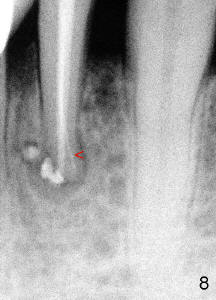

Sixty-two year old Chinese man presented to my office for new patient exam in June 2009. He has history of bruxism and wears night guard (Fig.1). The tooth #25 has incisal composite (*) with mild percussion. PAs show + PARL associated with #25 (Fig.2) and possible missing one canal (Fig.3; arrowheads point to possible 2nd root). RCT retreat was suggested. Extraction and implant were proposed as an alternative. In the next two 6-month appointments, he complained of mild pain in lower front tooth sometimes. RCT retreat was initiated on June 16, 2010. After removing composite, GP was removed with Chloroform and hand files. WL was determined by Root XZ at 15 mm. Debridement was done with hand files until #20 and rotary files until 30/.06 (Fig.4). The second canal was not found. It appears that some of GP was pushed outside of apical constriction (Fig.5 after Cavit). Twelve days later the patient returned to finish RCT retreat. It appears that symptoms improved after initiation of RCT retreat, although percussion is still mild. After removing Cavit and redebridement with #30 hand file, #10 precurved K file was inserted several times at different directions, hopefully getting into 2nd canal, which was not found. RCT filling was finished using AH Plus paste, master cone, lateral condensation with 1 medium fine accessory GP and vertical condensation (Fig.6). Composite build up was done immediately. Six months later, the patient insisted that pain is reduced substantially, but there is still mild percussion. PA shows persistent PARL (Fig.7 with outline with 2nd root (arrowheads)). Twelve months after RCT retreat, the patient is symptom-free, but objectively is not (including mild percussion and slightly enlarging PARL (Fig.8)). The 2nd canal is apparently lightly filled (red arrowhead).